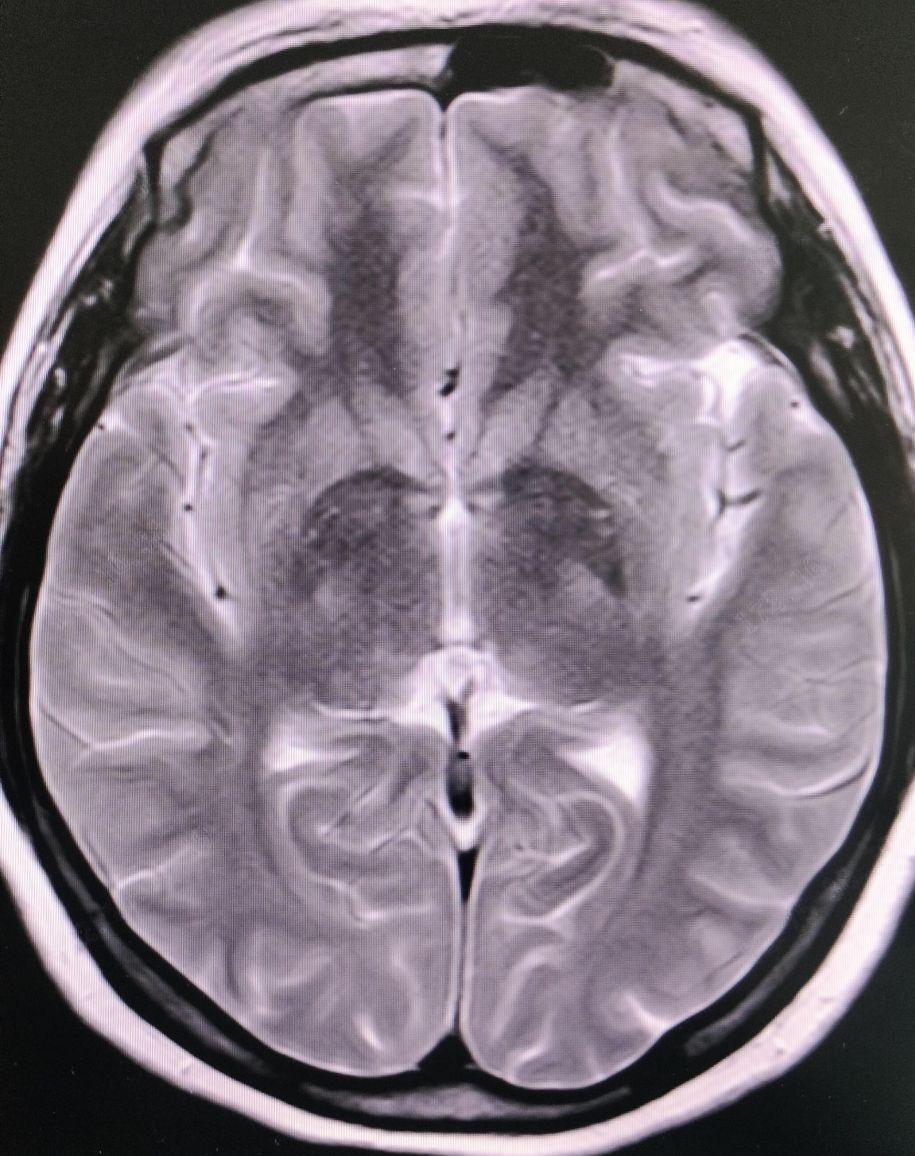

血常规:血红蛋白121g/L↓,淋巴细胞计数1.24*10^9/L↓,中性粒细胞计数1.98*10^9/L↑;生化检验报告:C反应蛋白<7mg/L; 尿常规:红细胞9个/μL↑,结晶200个/μL↑,凝血功能、肝肾功能、血糖、电解质、心肌酶谱、甲功三项、抗核抗体、心电图、胸片等均大致正常,乙肝三对、艾+丙+梅、核酸检测均阴性;双侧颈动脉彩超:右侧总动脉、颈内动脉、颈外动脉中内膜层毛糙、增厚;左侧颈总动脉、颈内动脉、颈外动脉、双侧椎动脉未见明显异常;双眼彩超:双眼玻璃体混浊声像;颅脑+双侧骶髂关节磁共振示:考虑双侧额叶缺血灶;骶髂关节MR平扫未见明显异常;右臀部皮下组织异常信号,考虑水肿或挫伤;所示盆腔少量积液;VOD:0.2(-0.25DS/-0.50DC*66=0.4),VOS:0.2-1(-0.25DS/-0.75DC*105=0.5);双眼睑无红肿下垂,结膜无充血,角膜内皮见大量羊脂状KP,以下方分布为主,前房中深,Tyn(+++),虹膜纹理清,瞳孔圆约3.0mm大小,对光反射灵敏;双眼晶体透明,玻璃体混浊,眼底模糊示:隐约见视盘界清,C/D约0.3,A/V约2/3,网膜平伏,未及明显出血、渗出,黄斑中心反光未及;双眼眼压: